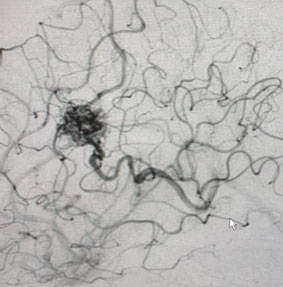

Angiogram (Figure 3 and 4) confirmed the presence of a deep left frontal AVM without any associated aneurysms.

Fig. 4